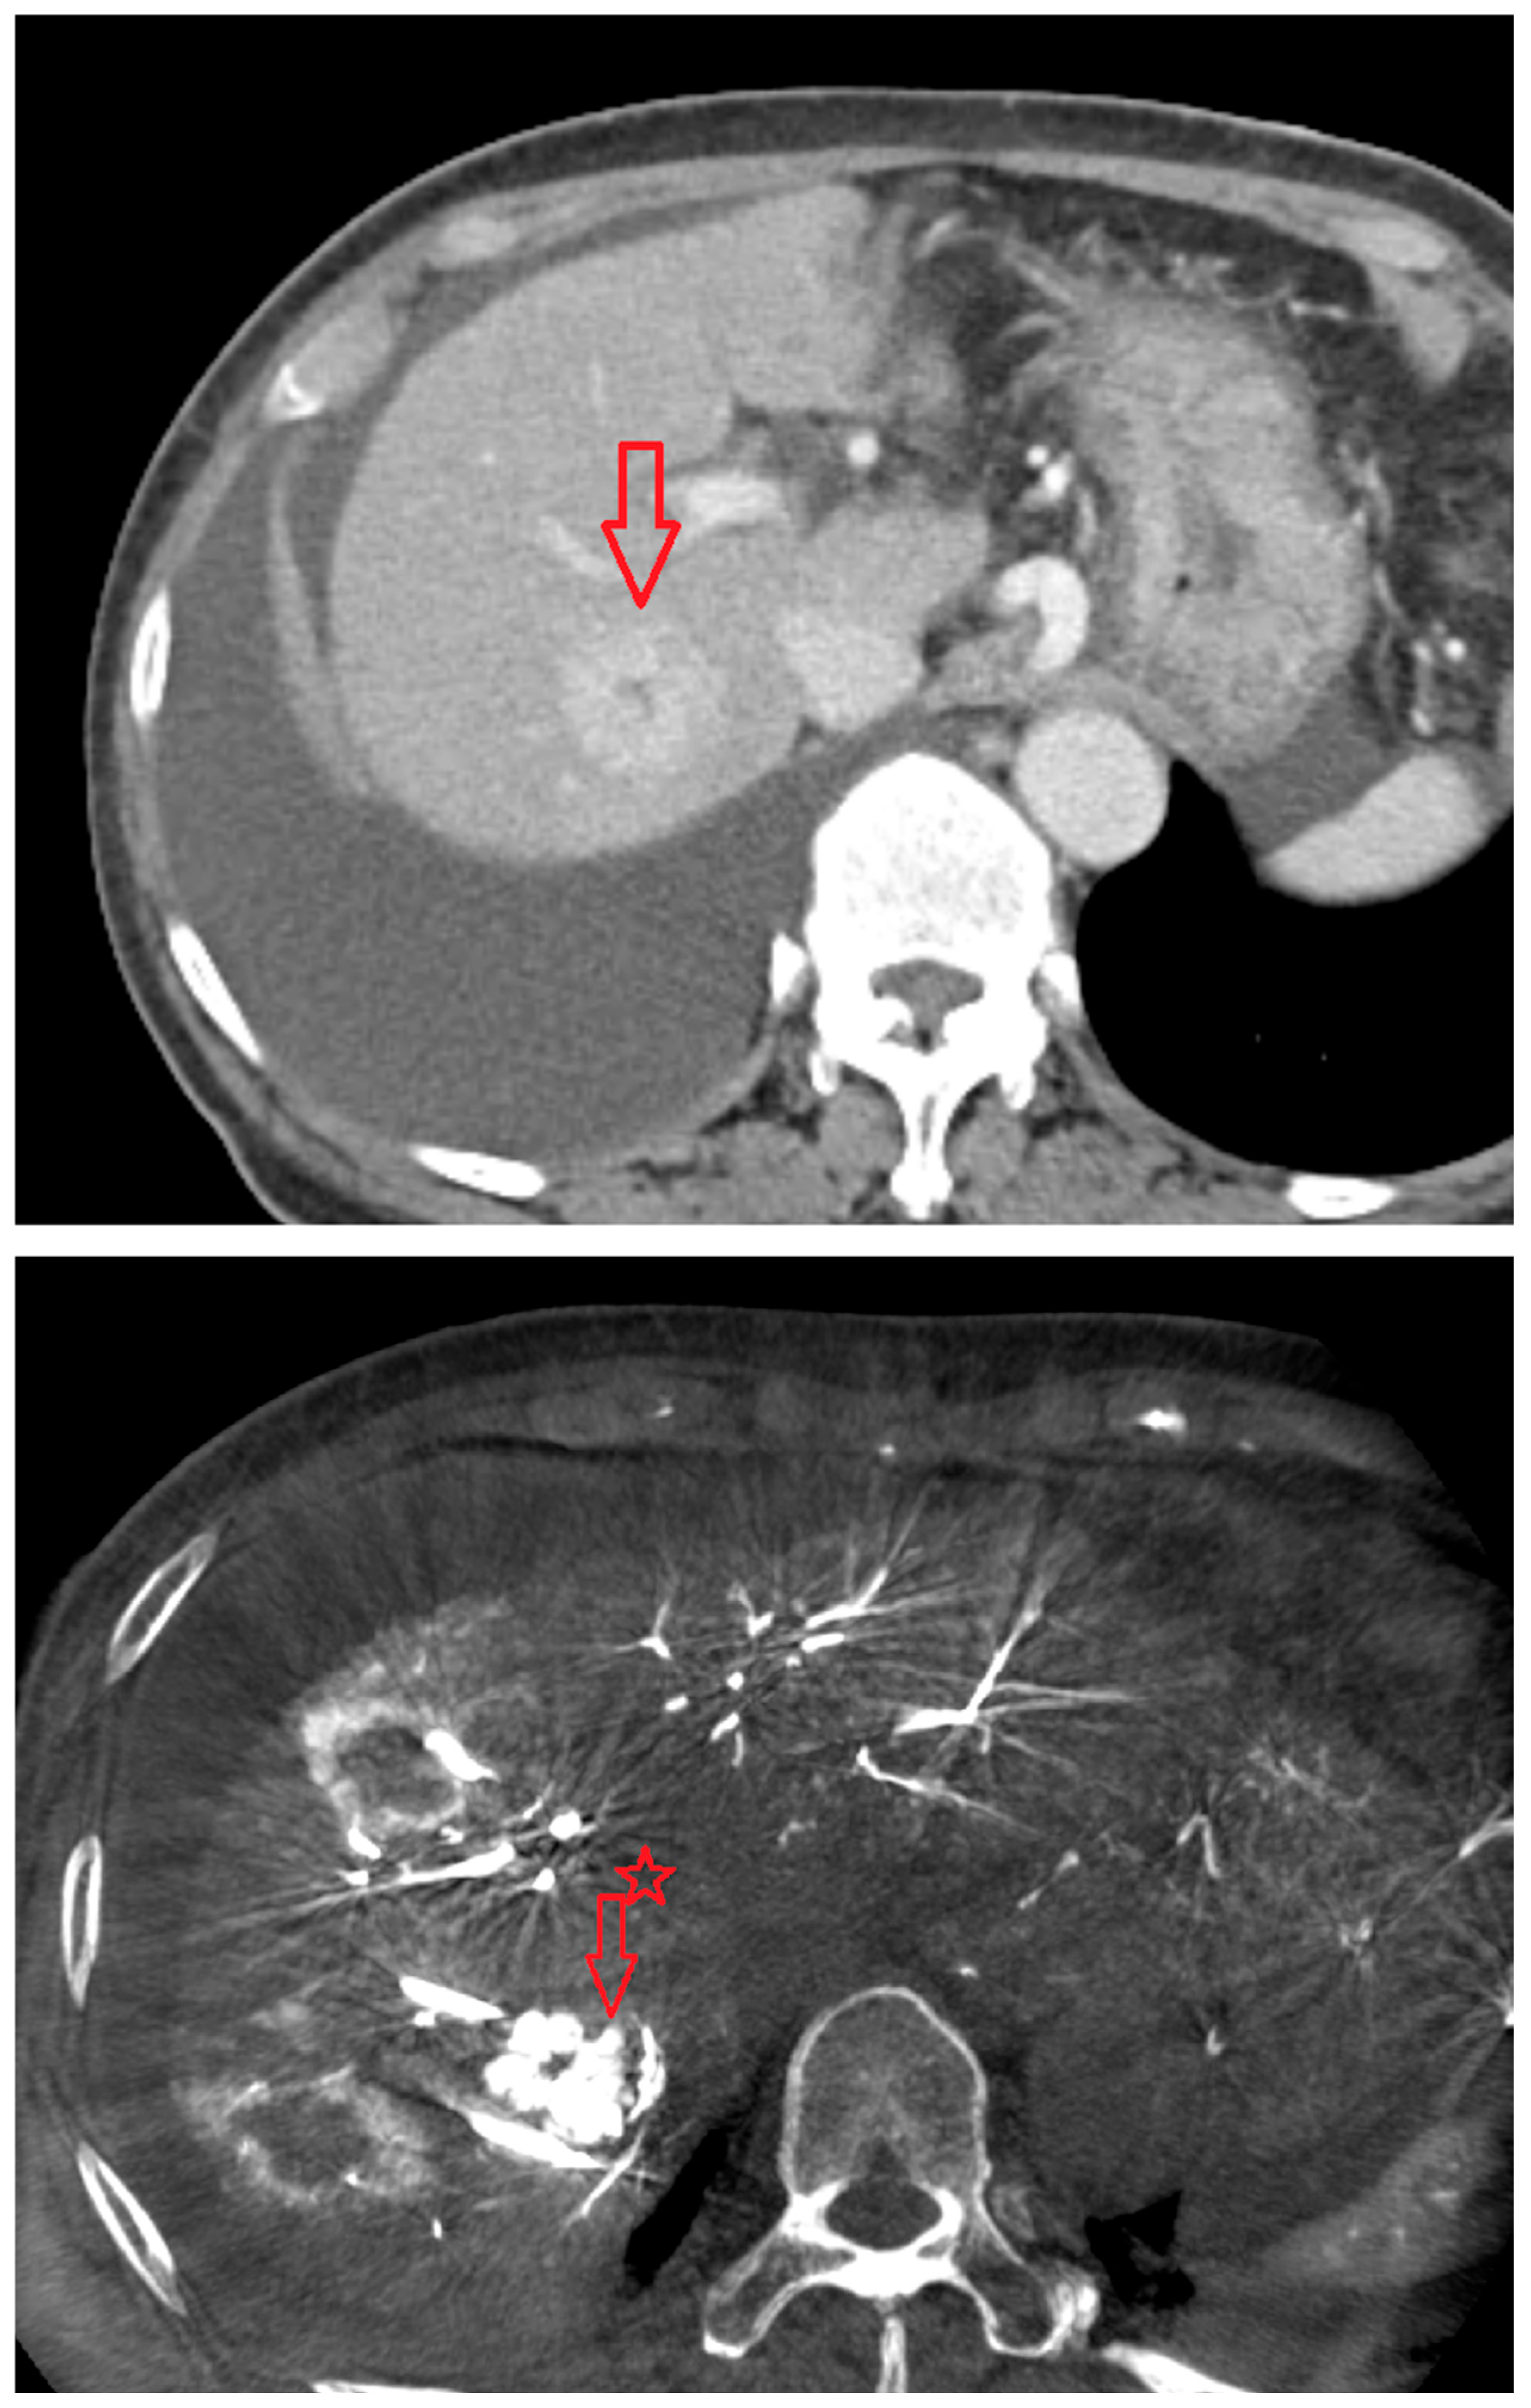

As shown in Figure 1, angio-CBCT allows for higher visibility of the target mass, as reflected in the ΔHU values. This can be visually confirmed in several cases. Representative cases in Figure 2 and Figure 3 demonstrate how the target mass is much more conspicuous to the operator on angio-CBCT compared to pre-procedural CT. In Figure 4, a mass, which was nearly invisible on pre-procedural CT, was identified through angio-CBCT, aiding the targeting process. Figure 5 shows a case where a mass with discordance between USG and CEUS was confirmed using angio-CBCT, leading to needle repositioning and achieving complete ablation. Finally, Figure 6 illustrates a case where a residual tumor was identified on angio-CBCT and re-ablation resulted in complete ablation.

Figure 3. CT images from other patient with hepatocellular carcinoma undergoing angio CBCT-guided RFA. (Top): pre-procedural CT (arterial phase). Red arrow and line = HCC mass (lesion 74.29 HU). (Bottom): intraprocedural angio CBCT. Red arrow = HCC mass (lesion 368.49 HU). ΔHU = 173.9 HU. (intra lesion − intra background) − (pre lesion − pre background).

Figure 4. Images from another patient with hepatocellular carcinoma undergoing angio CBCT-guided RFA. All red arrows indicate the HCC mass. (Left): pre-procedural CT (portal phase). (Middle): pre-procedural MRI (arterial phase). (Right): intraprocedural angio CBCT. (Intra lesion − Intra background = 432.7 HU).